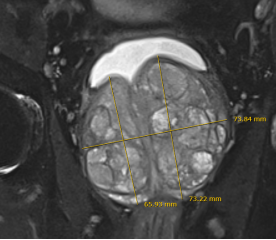

据了解,患者不仅年近八旬,还合并多重高危基础疾病:曾反复发生脑梗导致右侧肢体活动受限,体内留置冠脉支架,心功能评级为三级,根本无法耐受传统手术与常规麻醉。更棘手的是,患者前列腺体积达到惊人的164克,远超临床常见范围。根据前列腺增生分级标准,正常前列腺重量约20克,60克以上即为Ⅲ度重度增生,而该患者前列腺重量是正常水平的8倍多,属于临床罕见的“巨型前列腺”,此类病例一年难遇一次,手术难度极大。